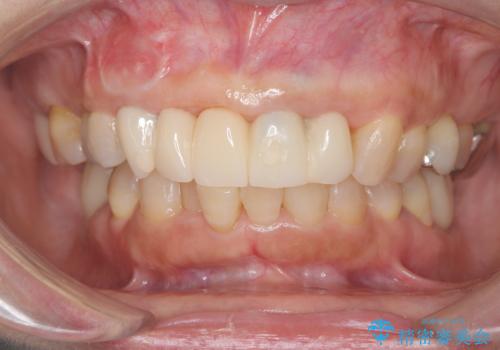

- 歯茎の大きな腫れを主訴に来院された患者様です。前歯5本にはブリッジが装着されていました。レントゲン検査より、右上3番に大きな根尖病巣が認められ、さらに左上1、2番の支台歯にも破折があったため、抜歯を行いました。その後、インプラントを3本埋入し、オールセラミッククラウンのブリッジで補綴しました。

これだけ大きな病変があったにもかかわらず、痛みがなく短期間で治療が終わったことに加え、被せ物の色も周囲の歯に調和し美しく仕上がったことに、大変ご満足いただけました。